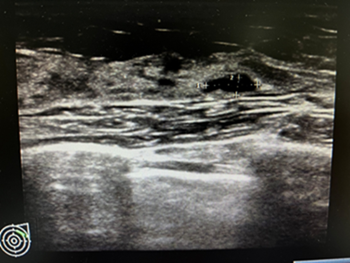

边界规整,良性纤维瘤,BI-RADS  3类